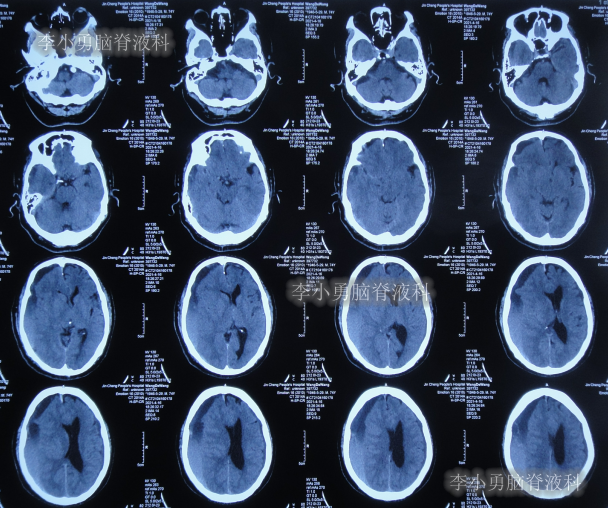

2021年4月14日(腰大池腹腔分流术后17天),头痛腿沉再次加重,复查头部CT示硬膜下血肿(图-3)。

图-3:2021年4月14日头部CT